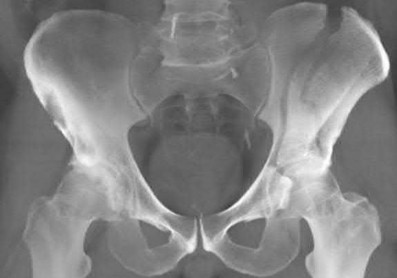

Question 11:

A poly-trauma patient presents hemodynamically unstable with an anteroposterior compression (APC-III) pelvic ring injury. A circumferential pelvic binder is requested to reduce pelvic volume and control hemorrhage. To be anatomically effective, the binder must be centered precisely over which of the following landmarks?

Correct Answer: Greater trochanters

Explanation:

For optimal mechanical advantage and effective reduction of an 'open book' pelvic fracture (APC type), a pelvic binder must be applied directly over the greater trochanters of the femurs. Applying it higher, such as over the iliac crests, is a common error that fails to adequately close the pelvic ring and can paradoxically open the true pelvis.